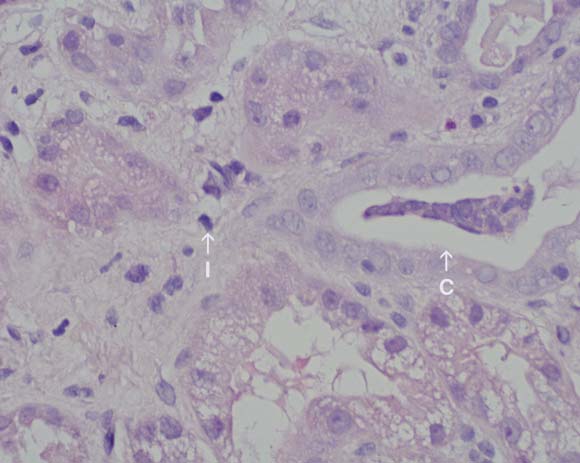

2 Renal biopsy specimen in Patient 2

Biopsy specimen from the renal cortex taken 2 days after presentation, showing an interstitial inflammatory infiltrate composed of lymphocytes and eosinophils (I), with mild acute tubular necrosis and a cellular cast (C). (Original magnification × 40; haematoxylin–eosin stain.)